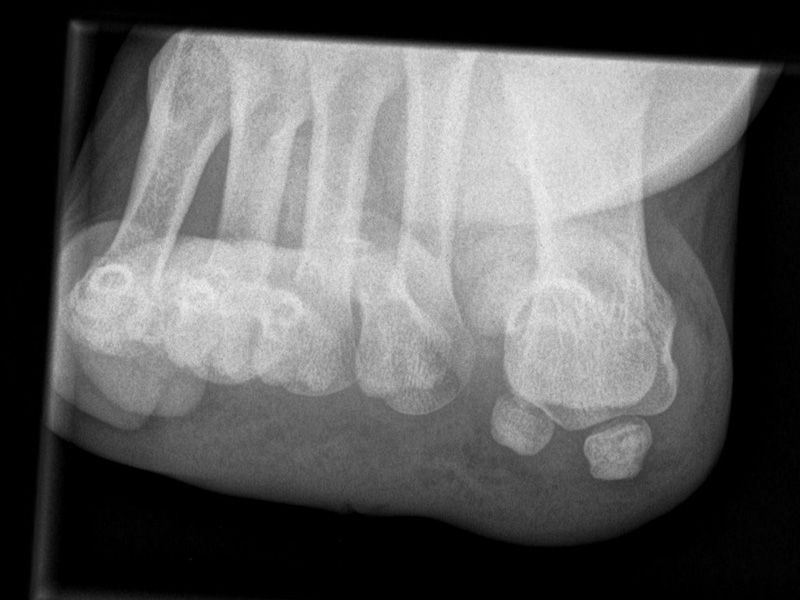

Stressaufnahme Calcaneocuboidgelenk

Indikation:

• V.a. Instabilität des Calcaneocuboidgelenks.

Positionierung:

• Patient liegt auf dem Rücken, das Knie gebeugt.

• Der Fuß wird in den Scheuber-Apparat gestellt.

• Die Röntgenkassette liegt horizontal.

• Der Zentralstrahl wird auf das Calcaneocuboidgelenk zentriert.

• Die Röntgenröhre steht 0° vertikal.

• Über eine mechanische Vorrichtung (z.B. Telos-Gerät, Scheuba-Apparat) wird kontrolliert eine Kraft von 15 daN (Dekanewton, entspricht ca. 15 kg) von medial in Höhe des Chopart-Gelenks appliziert. Der Gegenhalt erfolgt am lateralen Kalkaneus und am Mittelfuß.

Kennzeichen des Röntgenbildes:

• Darstellung des Calcaneocuboid-Gelenks.

• Beurteilung von Versatz und Aufklappbarkeit.

• Eine Aufklappbarkeit von > 10° gilt als pathologisch.

• Teilweise knöcherne Bandausrisse erkennbar.

Besondere Bemerkungen zum Beispielbild:

• Der Patient erlitt ein Mittelfußtrauma.

• Keine knöcherne Verletzung

• Aufklappbarkeit des Calcaneocuboid-Gelenks mit Versatz.

• Kleines Os tibiale externum medial ohne Krankheitswert.